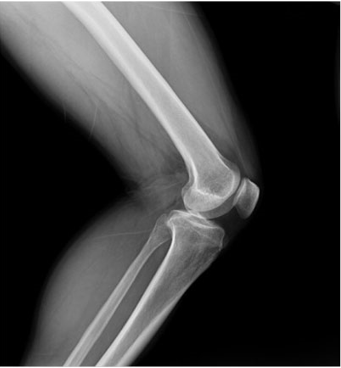

傾斜角度1